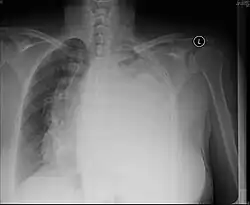

Post-operative changes

A pneumonectomy is a surgical procedure in which an entire lung is removed. A common reason for performing this procedure is for lung cancer originating in the lung itself.[19] This leads to a mediastinal shift towards the empty side of the thorax. Notably, patients can experience post pneumonectomy syndrome due to a severe mediastinal shift. This presents as difficulty breathing due to a shift of airways and rotation of the heart and great vessels. On x-ray, white out of the operated side and hyperinflation of the remaining lung is often observed.[20]